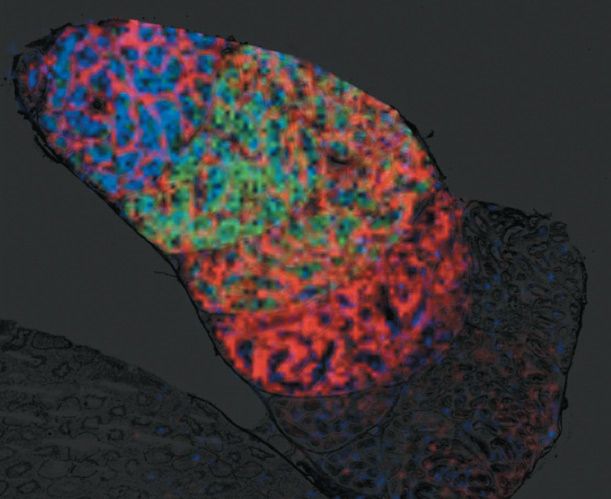

The unique ability of MALDI imaging to visualize molecules in situ has significantly advanced the study of this complex biology. Figure 4 shows a two-dimensional (2D) image of a rat epididymis head with highlighted peptides possibly involved in the maturation of sperm during its transit through the organ (14). Figure 5 illustrates the latest work in Pineau's lab: the creation of 3D images (15). The process of capturing a 3D MALDI imaging model of an organ begins with making many hundreds (or thousands) of sections through the organ. Each section is measured and the data are combined in software to create the final picture. The resulting data sets are huge-in the terabyte range-but once completed, a dataset can be mined for information for many years.

Figure 4: Molecular image of sperm transit in the rat epididymis by MALDI imaging MS. Peptides specific to maturing spermatozoa during epididymal transit can be visualized simultaneously. Signal overlay of three specific peptides corresponding to m/z 5470, 6177, and 18,746 is visualized in different colors. An 80-µm lateral image resolution is mandatory to resolve the organ structures.

Figure 5: Three-dimensional mass spectrometry imaging view of a rat epididymis head. PLSA computation in SCiLS software with restricted mass range (m/z 250-1650). Left: m/z corresponding to a metabolite localized in the vas efferens area. Right: m/z corresponding to a metabolite expressed along the tubule.